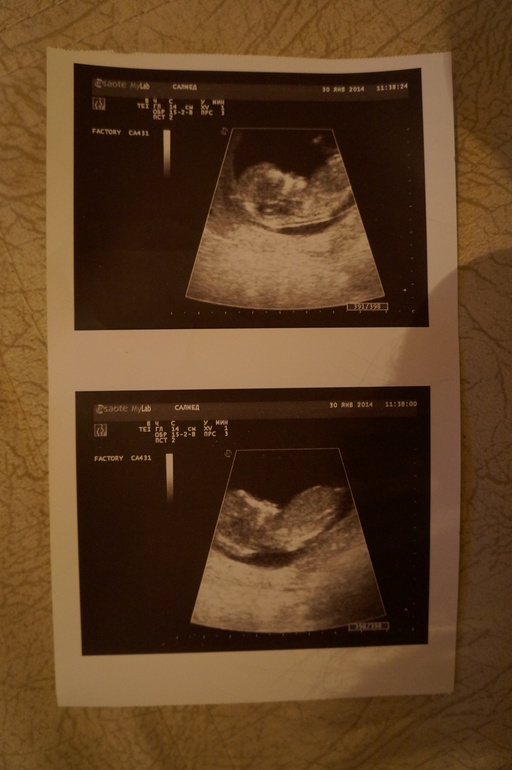

30 были на УЗИ все у нас хорошо! Срок 12н 2д ( по мес 12.3). Опять по задней стенке. Сказали пол у нас еще одна принцесса! Хотелось мне конечно очень мальчика, но и девочку я очень жду и люблю. Маненько конечно поплакала,но главней здоровье а не пол.

А вот первые снимки моей принцессы( не очень удачные))

УЗИ( сохраню для сравнения с третьей беременность,когда за сыном пойду))